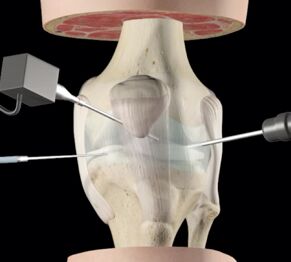

L’intervento è effettuato in artroscopia (con tecnica mini-invasiva, senza “aprire” l’articolazione ma lavorando attraverso fori e con l’utilizzo di una telecamera - Fig. 4).

Fig. 4. – Rappresentazione grafica di Tecnica mini-invasiva di esecuzione Artroscopica in chirurgia del ginocchio.